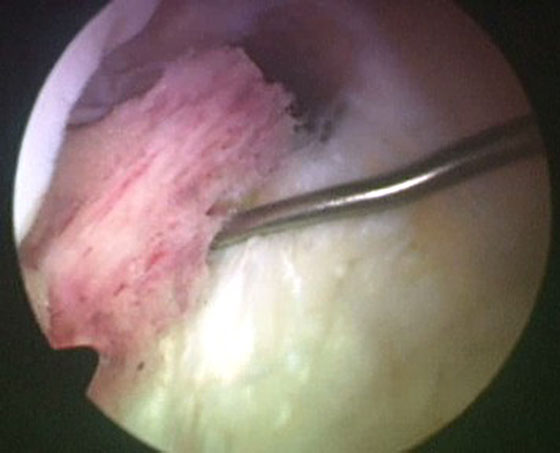

Se procede luego a realizar el portal posterointerno. Dado que no se reseca el remanente HPM, el espacio para acceder a la cápsula posterointerna se encuentra reducido, para ampliarlo realizamos una mínima “notchplastia” en la parte posterior del cóndilo interno (Fig. 4). Con la visión desde el portal anterointerno colocamos un switcher, de los utilizados en cirugía de hombro, desde el portal anterolateral ubicándolo entre el remanente ligamentario y el cóndilo interno (Fig. 5). Luego se pasa la cánula de irrigación guiada por el switcher y se accede con la óptica a la cápsula posterointerna, bajo visión directa colocamos una aguja espinal para localizar el portal, completando con bisturí para luego colocar la cánula de trabajo (Fig. 6). En este punto se vuelve a pasar el artroscopio al portal anterointerno, se introduce el shaver por la cánula del portal posterointerno, y se realiza la limpieza de la capsula posterior, siempre con la hoja de corte hacia anterior para evitar la lesión de estructuras vasculonerviosas. Se continúa alternando los portales anterointerno y posterointerno con visión, shaver, pinza basket y raspas de 90º, hasta completar la desinserción de cápsula posterior e identificar el remanente distal del ligamento sin afectar la inserción. En los casos en que la lesión ha sido en la sustancia colocamos la guía tibial distal a la inserción tibial (Fig. 7). Si la lesión ha comprometido la inserción tibial, levantamos la cicatriz que encontremos y colocamos la guía por debajo del remanente (Fig. 8). Para la introducción de la guía sin lesionar los remanentes ni el LCA se coloca la óptica en el portal anteroexterno y se controla el ingreso de la guía por el espacio entre el remanente y el cóndilo interno (Fig. 9). Se pasa el clavo guía, siempre cuidando de llegar en forma motorizada hasta contactar la cortical posterior y se completa el pasaje golpeando con martillo para evitar una salida brusca del mismo. Se pasa la fresa canulada del diámetro adecuado, protegiendo la emergencia de la misma con una cureta. Una vez completado el túnel tibial, se pasa un alambre o cable desde el orificio externo tibial hacia proximal, con visión en portal posterointerno, al ver emerger el alambre o cable por el orificio tibial posterior, se vuelve la óptica al portal anterointerno para controlar el pasaje de un grasper desde anteroexterno a través del intervalo entre HAL y LCA, y dirigirlo hacia posterior (Fig. 10); se vuelve con la óptica al portal posterointerno y se visualiza la recuperación del alambre o cable con el grasper hacia la parte anterior de la rodilla (Fig. 11). Se amplía el portal anteroexterno y se anuda la sutura tractora del injerto al alambre o cable, y traccionando desde el orificio distal del túnel tibial se hace ingresar el injerto en forma retrógrada a la articulación y, luego, al túnel tibial por su orificio posterior. En caso que se utilice el injerto de tendón cuadricipital la parte tendinosa irá al túnel tibial y el bloque óseo al femoral. Una vez ingresado el injerto al túnel tibial, se vuelve la óptica al portal anterointerno, en el portal anteroexterno tendremos la sutura tractora del extremo “femoral del injerto”, es aconsejable en este punto llevar el injerto lo más distal posible para tener mejor visión articular, enhebrar la sutura tractora en una cánula de unos 6 mm de diámetro, para asegurarse que la sutura tractora y la clavija pasasutura pasan por el mismo espacio sin incluir tejido sinovial o grasa retrorrotuliana (Fig. 12). Se procede a pasar la aguja pasasutura por el túnel femoral, saliendo por las partes blandas de la parte medial de la rodilla, se tracciona y se asciende el injerto colocándolo en el túnel femoral. En caso que el injerto tenga bloque óseo puede ser necesario redirigir el mismo para ubicarlo en el túnel femoral, para esto ubicamos la visión en el portal anteroexterno y por el portal anterointerno utilizamos el trocar romo o el palpador para realizar una polea y mejorar la tracción para que ingrese el taco óseo en el túnel femoral (Fig. 13). Luego se realiza la fijación femoral con tornillo de interferencia de titanio o biodegradable. A continuación liberamos el manguito neumático, porque creemos que produce un espasmo en los isquiotibiales que dificulta la reducción de la tibia, dejamos pasar unos minutos que utilizamos para colocar un tornillo maleolar con arandela, distal al orificio externo del túnel tibial para realizar una segunda fijación de la parte tibial. Preferimos hacerlo antes de colocar el tornillo interferencial, porque esto generará una presión hacia posterior de la tibia. Se realiza la reducción tibial en 90° de flexión de la rodilla, se tracciona del injerto y se coloca el tornillo de interferencia tibial, luego la sutura remanente (polyester 5) se anuda en el tornillo maleolar completando la 2da fijación. Por último se constata con una nueva visión articular la posición y tensión del injerto (Fig. 14).

Figura 13